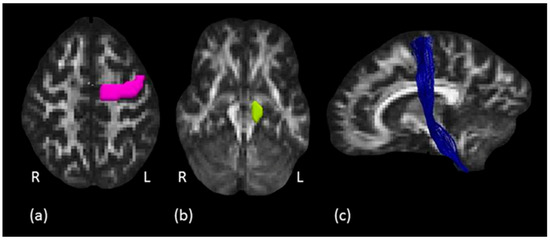

Structure of the Motor Descending Pathways Correlates with the Temporal Kinematics of Hand Movements

The projection system, a complex organization of ascending and descending white matter pathways, is the principal system for conveying sensory and motor information, connecting frontal and sensorimotor regions with ventral regions of the central nervous system. The corticospinal tract (CST), one of the [...] Read more.

The projection system, a complex organization of ascending and descending white matter pathways, is the principal system for conveying sensory and motor information, connecting frontal and sensorimotor regions with ventral regions of the central nervous system. The corticospinal tract (CST), one of the principal projection pathways, carries distal movement-related information from the cortex to the spinal cord, and whether its microstructure is linked to the kinematics of hand movements is still an open question. The aim of the present study was to explore how microstructure of descending branches of the projection system, namely the hand motor tract (HMT), the corticospinal tract (CST) and its sector within the internal capsule (IC), can relate to the temporal profile of reaching and reach-to-grasp movements. Projection pathways of 31 healthy subjects were virtually dissected by means of diffusion tractography and the kinematics of reaching and reach-to-grasp movements were also analyzed. A positive association between Hindrance Modulated Orientation Anisotropy (HMOA) and kinematics was observed, suggesting that anisotropy of the considered tract can influence the temporal unfolding of motor performance. We highlight, for the first time, that hand kinematics and the visuomotor transformation processes underlying reaching and reach-to-grasp movements relate to the microstructure of specific projection fibers subserving these movements. Full article

Show Figures

Figure 1